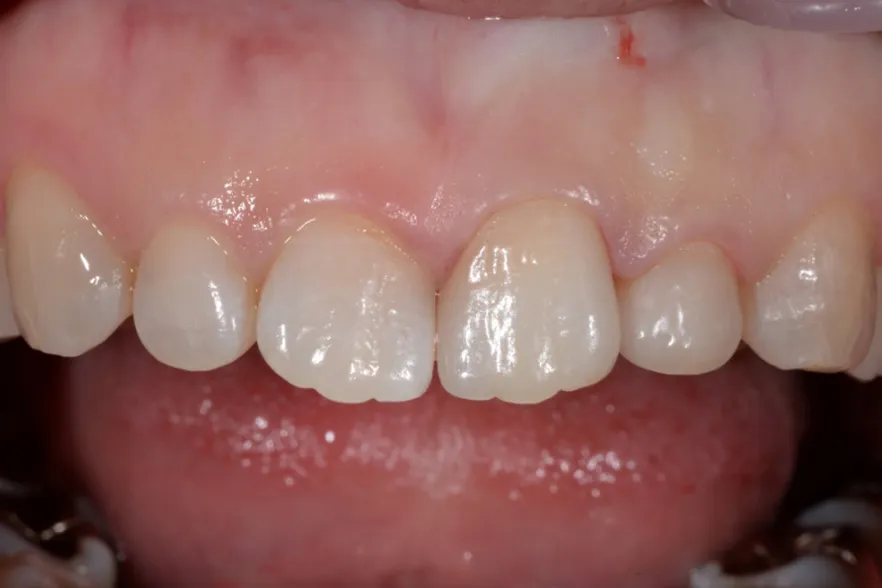

case2

Before

After

治療内容 | 口腔内診査〜カウンセリング 歯周初期治療 仮歯を入れ機能的な評価 最終的な型取り〜装着 |

---|---|

治療期間 | 1ヶ月〜2ヶ月 |

治療回数 | 5回 |

リスク | クリーニングにこない場合噛み合わせの確認ができないため装着していった人工物が割れてしまう可能性があるため、今後のメンテナンスが必須となる |

費用(税込) | 約¥143,000 |